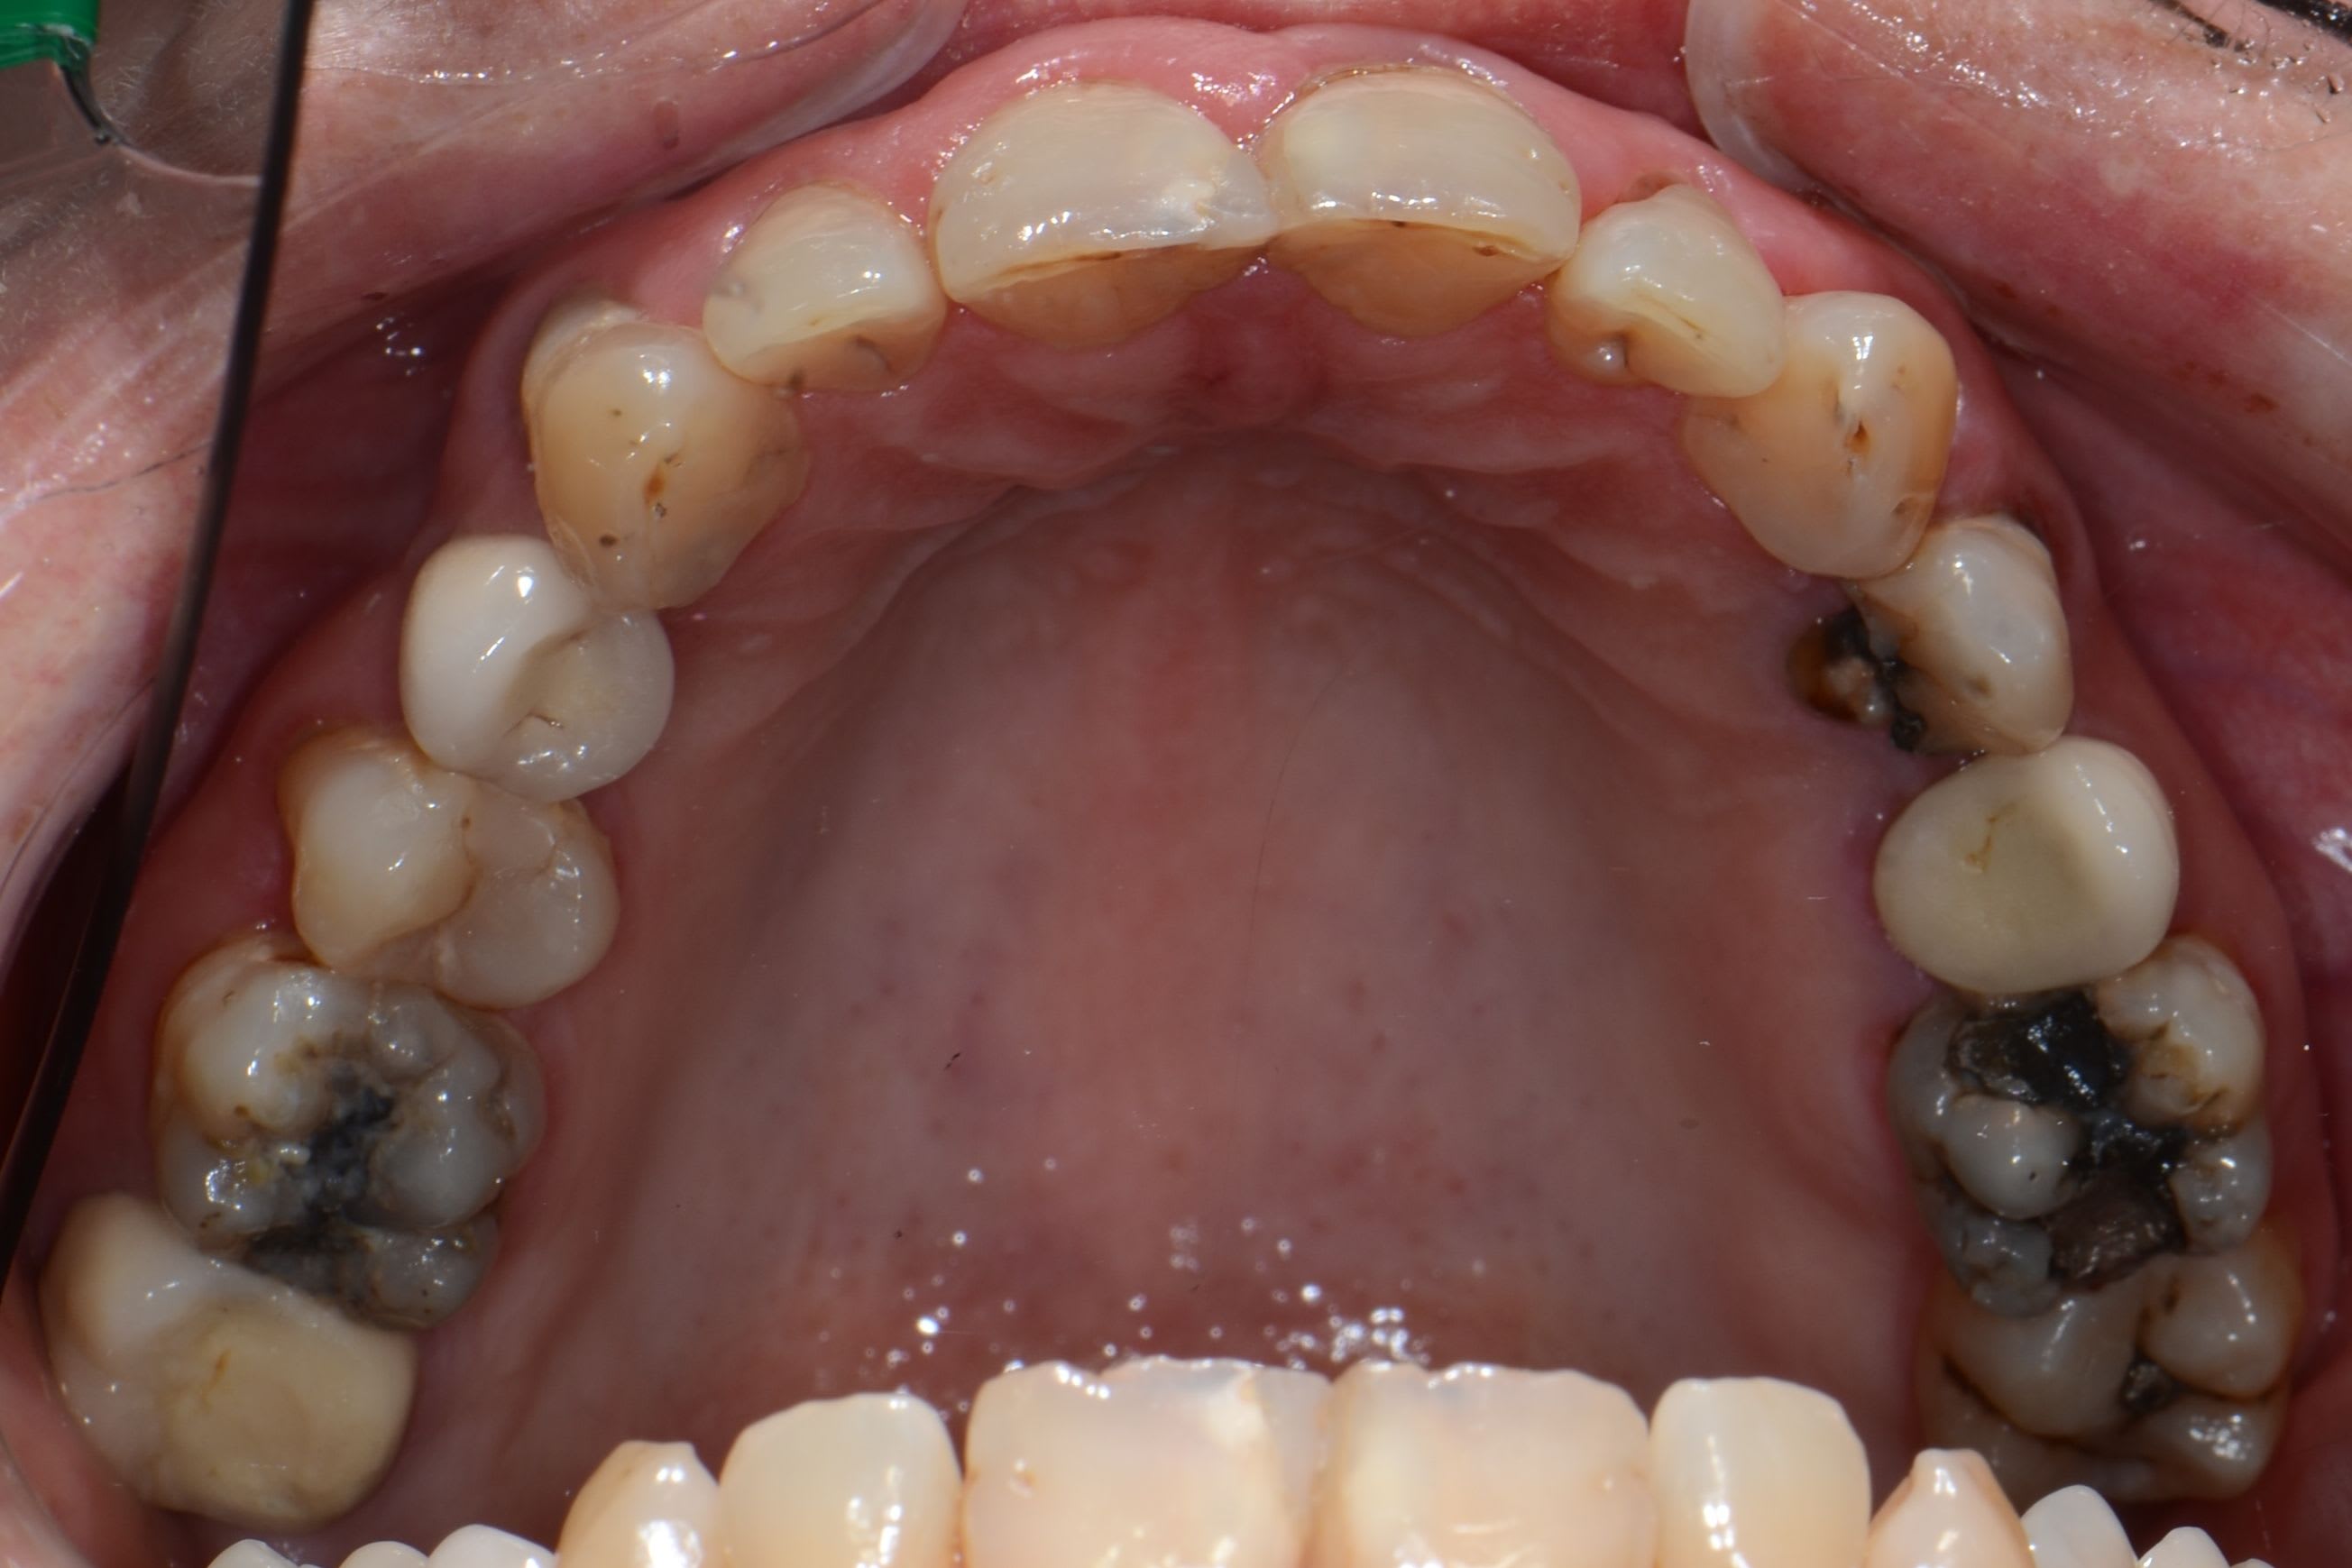

Nouvelle patiente 60 ans, pas de tabac, pas d'habitudes alimentaires prédisposantes mais syndrôme sec, très peu de salivation et ce depuis 2 ans.

A l'examen clinique, caries de collets typiques, la 45 a du être dévitalisée. Les caries sont plus importantes cliniquement que radiologiquement. Par ex les incisives mand étaient presque intégralement cariées en linguale (?).

Je lui ai fais un bilan et ai décidé de soigner les caries de collet au CVI (GC Equia forte). La 24 et 45 seront couronnées.

Le souci est que malgré la fluoration (flucaril bi-fluoré), motiv à l'hygiène ca progresse quand même.

J'ai l'impression que ca ne finira jamais, sans parler du coté relativement inesthétique du cvi.